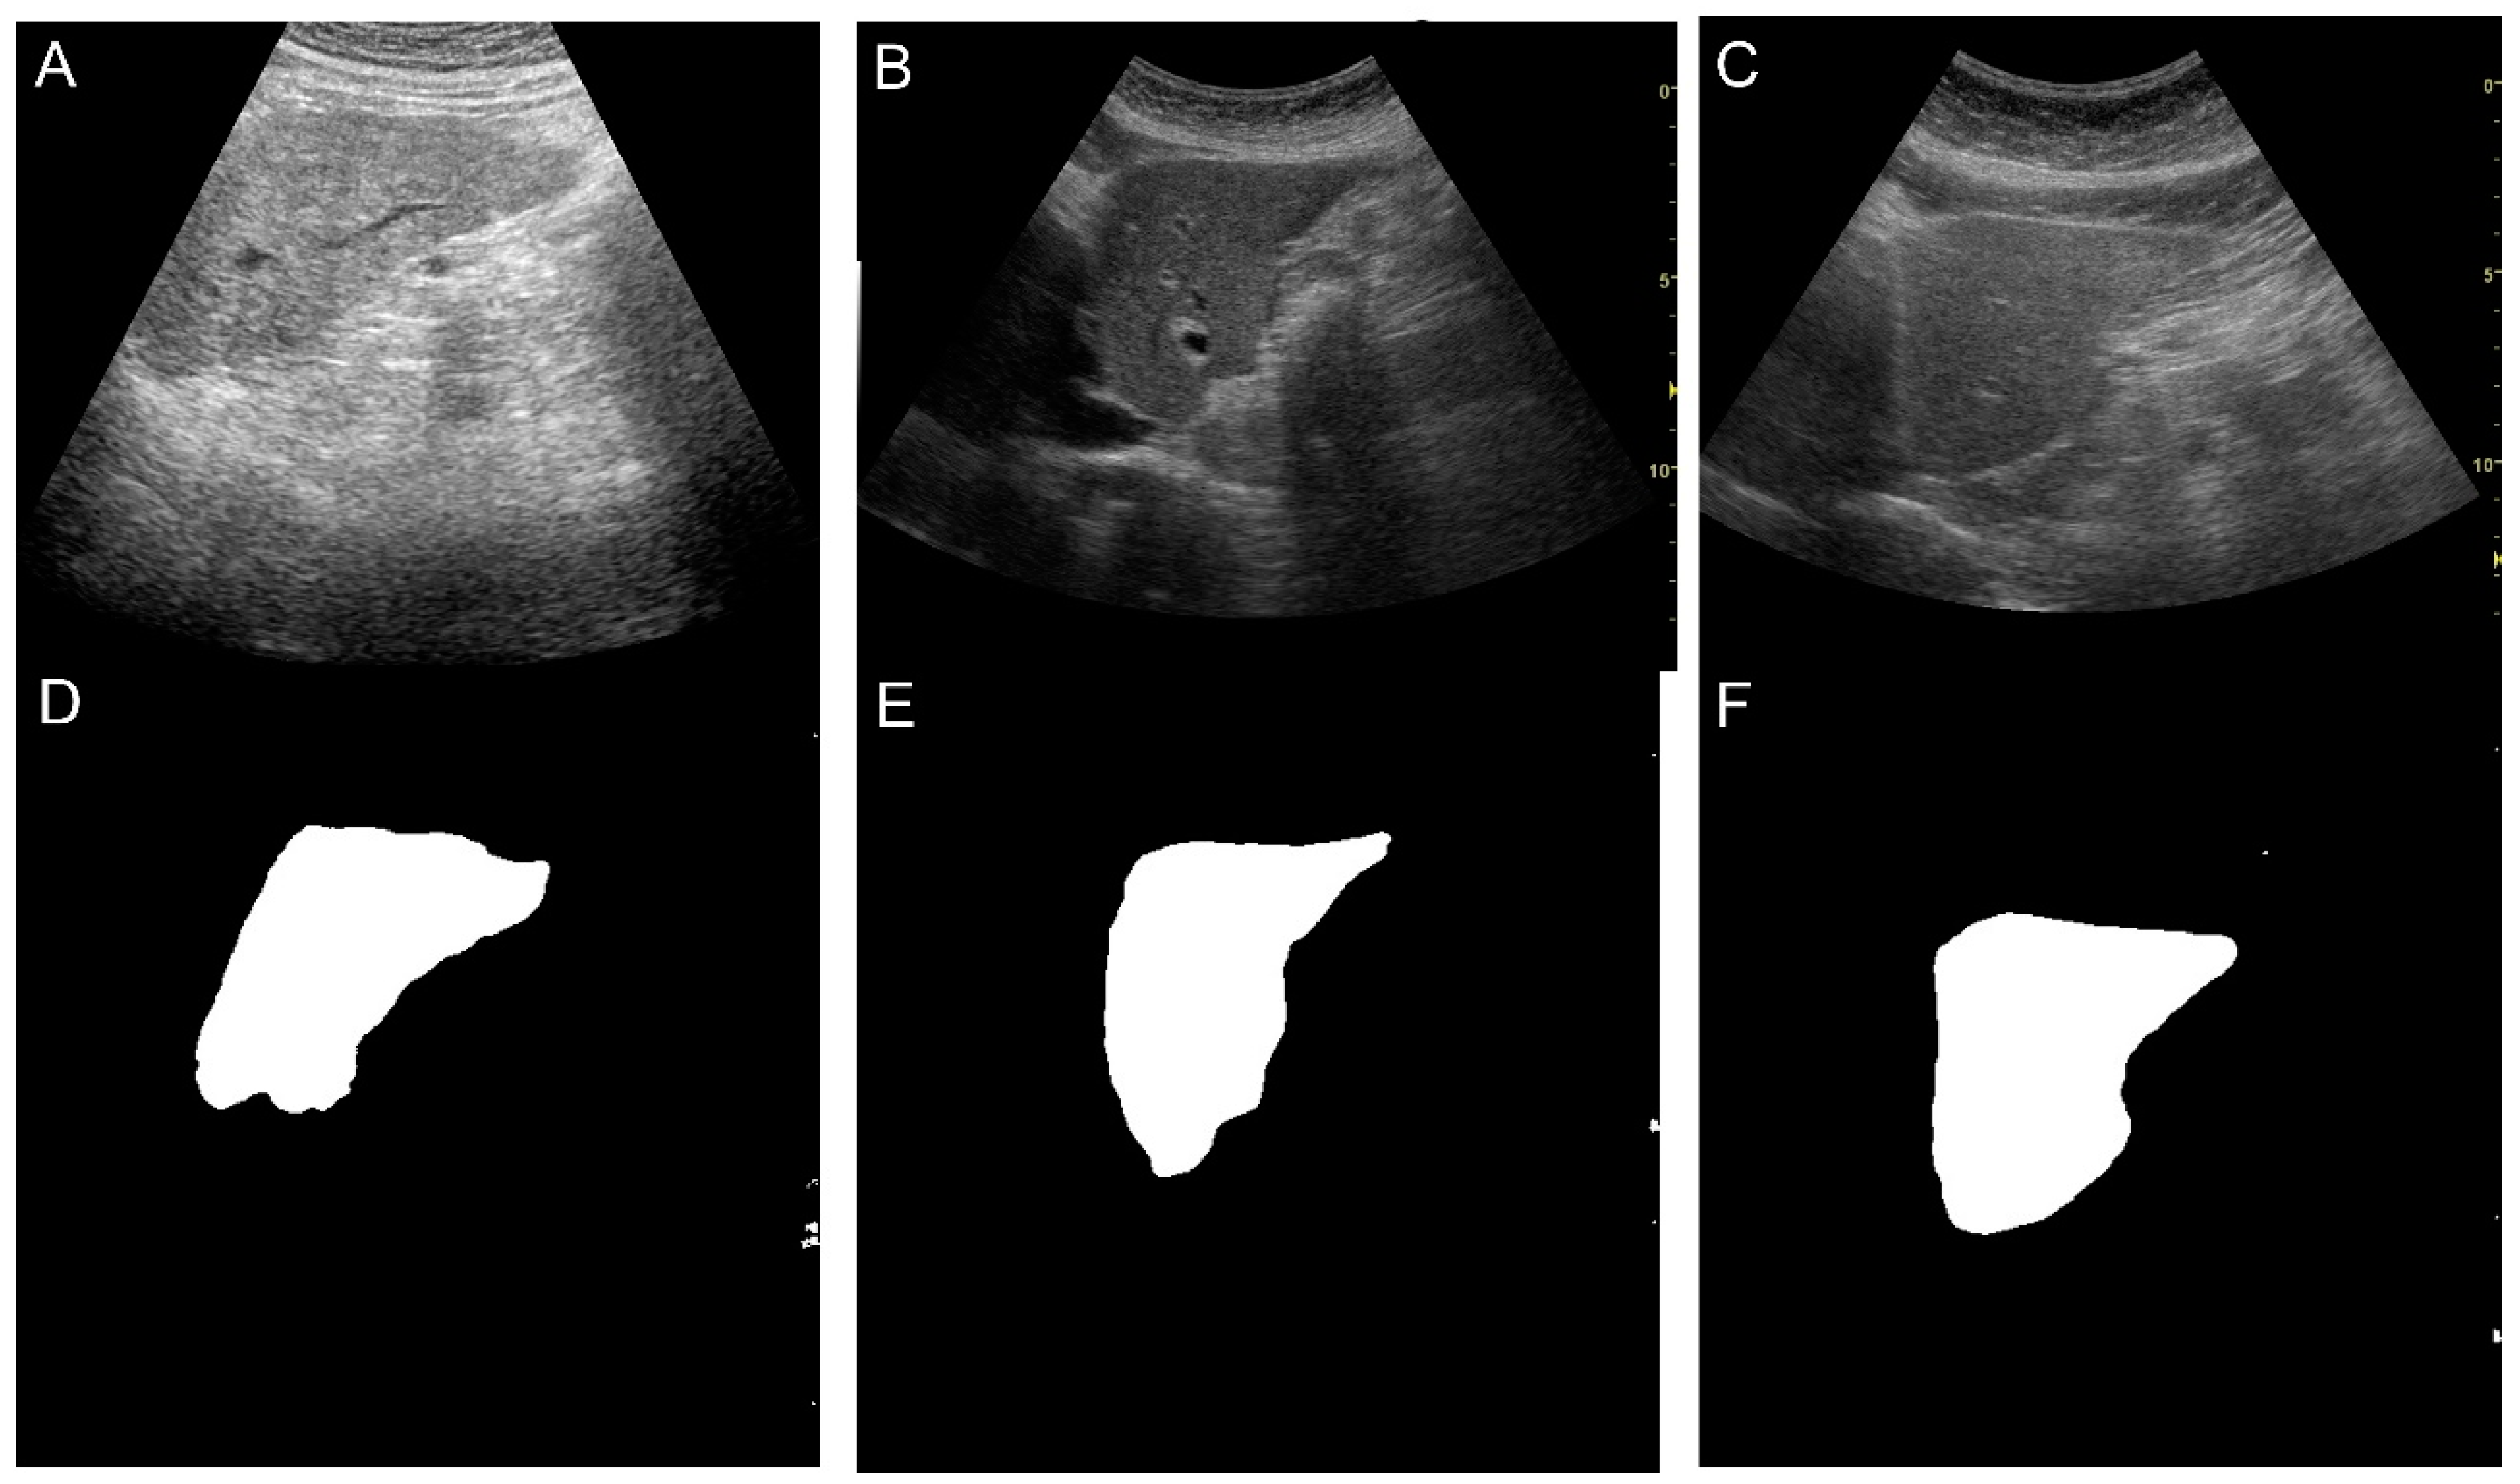

Đặc biệt ở Việt Nam, nơi nhiều người bệnh có thể đồng mắc thêm viêm gan B, do rượu hoặc các bệnh tim mạch, việc tiếp cận đa nguyên nhân và phân tầng nguy cơ sẽ giúp quản lý bệnh hiệu quả hơn. Bác sĩ cho biết, ngoài các phương pháp chẩn đoán quen thuộc như siêu âm, các công cụ tiên tiến hơn đang được nghiên cứu ứng dụng để đánh giá chính xác mức độ xơ hóa gan, từ đó đưa ra quyết định can thiệp kịp thời.

Trước đó, tại Hội thảo khoa học "Nâng tầm chẩn đoán bệnh lý gan: Tối ưu hóa hiệu quả và độ chính xác nhờ công nghệ và AI trong siêu âm", các chuyên gia nhận định nhờ sự phát triển của công nghệ, siêu âm định lượng độ cứng và độ nhiễm mỡ gan đã trở thành một công cụ đột phá.

Phương pháp này cho phép định lượng chính xác mức độ xơ hóa và nhiễm mỡ gan mà không cần bất kỳ can thiệp xâm lấn nào. Đặc biệt, khi kết hợp với Trí tuệ nhân tạo (AI), dữ liệu được phân tích nhanh chóng, mang lại kết quả đồng nhất và có độ lặp lại cao, từ đó hỗ trợ các bác sĩ đưa ra quyết định lâm sàng tối ưu một cách hiệu quả và tin cậy hơn.

Bên cạnh đó, những trường hợp thực tiễn tại bệnh viện cho thấy góc nhìn sâu sắc hơn không chỉ về cách ứng dụng AI và siêu âm hiện đại trong chẩn đoán, mà còn là tầm quan trọng của việc can thiệp sớm và theo dõi định kỳ trong điều trị các bệnh lý gan. TS.BS Nguyễn Công Hựu, Giám đốc Bệnh viện E, cho biết với sự hỗ trợ của AI góp phần chẩn đoán và quản lý bệnh lý gan tại Việt Nam ngày một hiệu quả, cải thiện chất lượng cuộc sống cho hàng triệu người bệnh trên khắp cả nước.